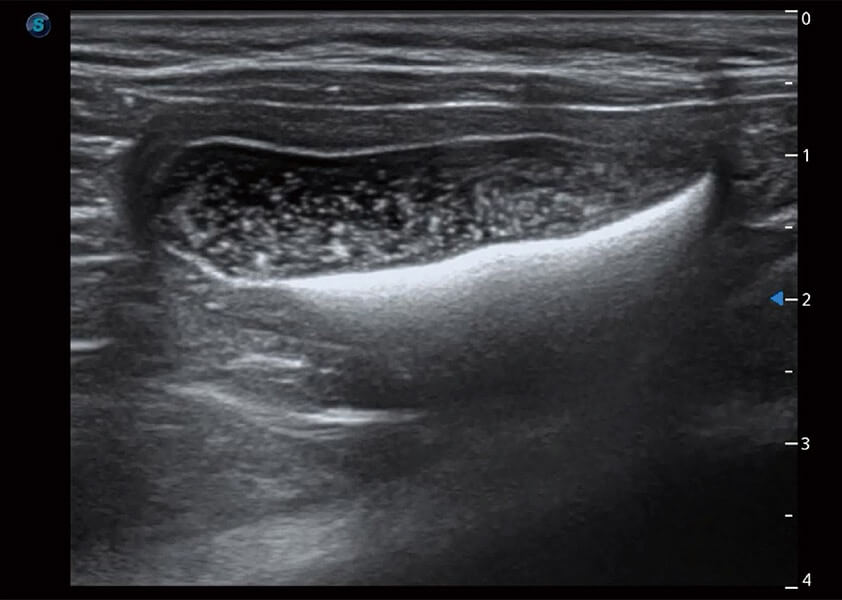

ProPet 60 作为一款高端台式动物超声设备,为动物医生的日常诊断提供了一系列贴合动物临床需求、解决临床实际问题的高级成像功能。凭借全系列高清探头,满足医生对腹部、心脏、生殖、浅表、肌骨等成像的所有需求,切实帮助您提升检查效率,提高诊断信心。

动物是人类最亲密的朋友和最值得信赖的伙伴。1xBET也一直致力于探索动物专用的超声影像解决方案。 全新推出的ProPet系列,是1xBET在动物超声影像智能化、专业化、精准化的一次跨越式革新。动物不能用言语来表述自己的不适,通过超声影像,ProPet系列搭建了动物医生与不同物种沟通的“桥梁”,为动物医生注入了“治愈之力”。